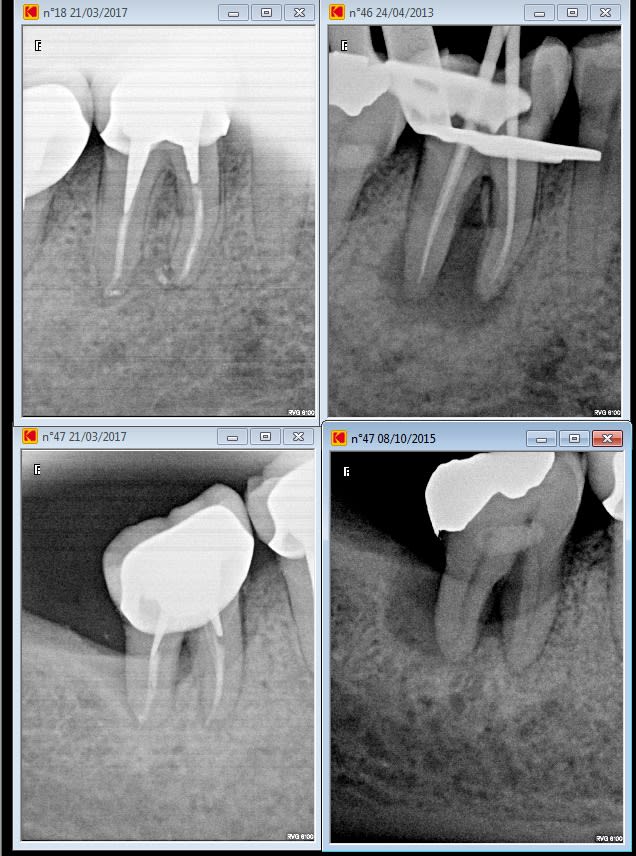

Cette patiente était ma dernière de la journée..... Donc parfaitement détendu j'ai eu le temps de bien l'éclairer. On vire le compo cassé photo et explication :

Voyez si on s'arrete là on peut faire un onlay et garder votre dent vivante.....

C'est 400 euros remboursés 40 par la sécu + votre mutuelle il vous reste 360 euros à charge.

C'est trop cher. Ah ?